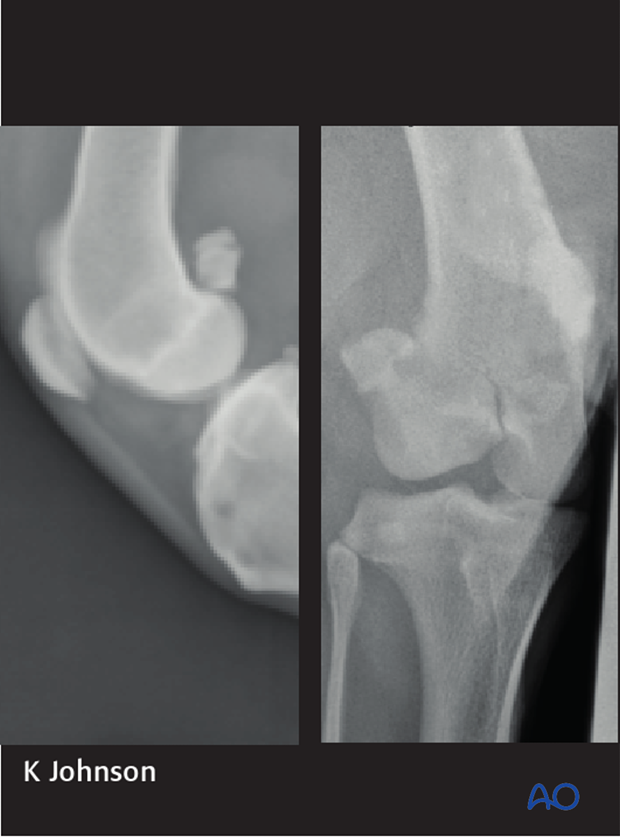

Shown are mediolateral and a slightly oblique craniocaudal radiograph highlighting a 33-B1 fracture of the distal femur.

33-B fractures are articular fractures of one of the femoral condyles that occur secondary to compressive and torsional forces on the distal femur. One or more of the cruciate or collateral ligaments may be attached to the fracture fragment. These fractures may or may not be displaced. Fixation should be performed as soon as possible to avoid abrasion damage of the articular surface, ligaments, and menisci.

Good quality mediolateral and craniocaudal radiographs are essential for fracture evaluation. If there is minimal displacement of the fragments, diagnosis may be difficult. Oblique projections and mediolateral stressed views of the distal femur might be helpful.